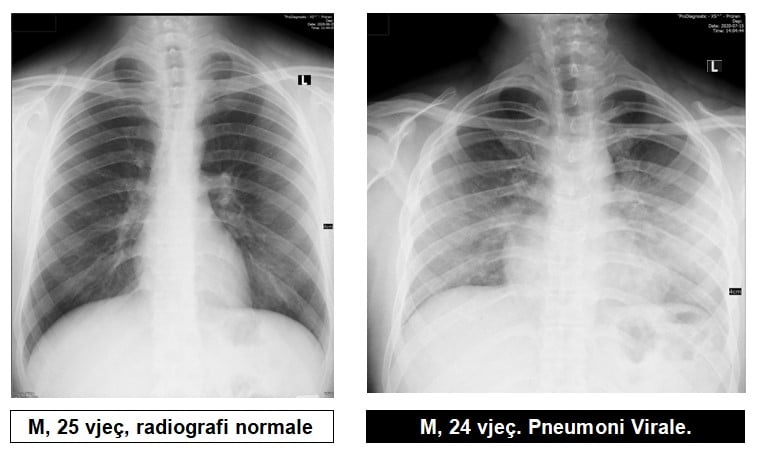

Radiologu në Spitalin Rajonal të Prizrenit, Sylejman Krasniqi tregon pamjet e mushkërive të pacientëve me pneumoni virale.

Imazhet e mushkërive me pneumoni virale